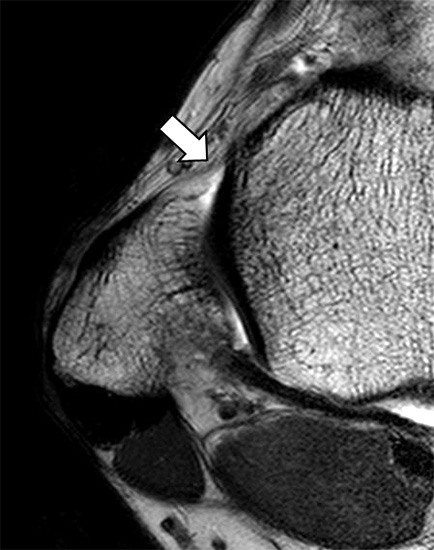

Ein diagnostisches Problem stellen nicht dislozierte Avulsionen talar- oder fibulaseitig dar, da diese eine scheinbare Bandkontinuität vortäuschen können. Selbst geringe osteo-ligamentäre Dehiszenzen lassen sich jedoch in der hochauflösenden MRT multiplanar dokumentieren und somit die Diagnose einer nicht dislozierten Avulsion mit hoher Sicherheit stellen (Abb. 4 a und b). Als weitere Alternative sind die Anfertigung schräg sagittaler Schichtführungen entlang der Längsachse des LFTA möglich, die die osteo-ligamentäre Übergänge klar visualisieren (Abb. 5). Problematisch bleibt jedoch die Differenzierung einer kompletten LFTA-Ruptur vom interstitiellen Typ mit erhaltener Kontinuität zu einer Partialruptur mit diffuser, fibrillierender Bandauftreibung.

Physiologische Bandlücke (Pfeil)

Abbildung 9b

Eine Ursache der falschen Diagnose einer LFTA-Ruptur ist die Fehlinterpretation der physiologische Bandlücke zwischen dem LFTA und der vorderen Syndesmose als traumatischer Banddefekt (Abb. 9 b).